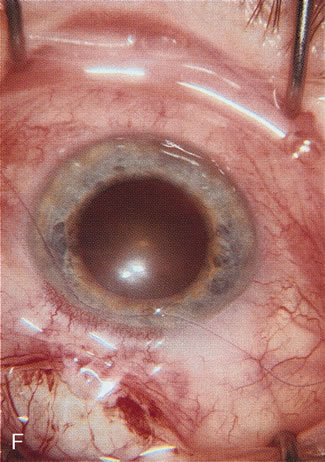

Fig. 6. ECCE following trabeculectomy. The larger corneal incision associated with ECCE leads to a host of problems that are typically less severe with small incision cataract surgery. With improved phacoemulsification techniques, this type of incision is infrequently encountered. This bleb failed following ECCE, and topical antiglaucoma therapy was restarted. Long-term wound drift; astigmatism, and corneal decompensation are additional visual factors. However, when the nucleus is brunescent and phacoemulsification risky, surgeons with the skill to convert to ECCE through a clear corneal incision are at a significant advantage. This 11-mm free hand incision takes considerable practice and skill to master.